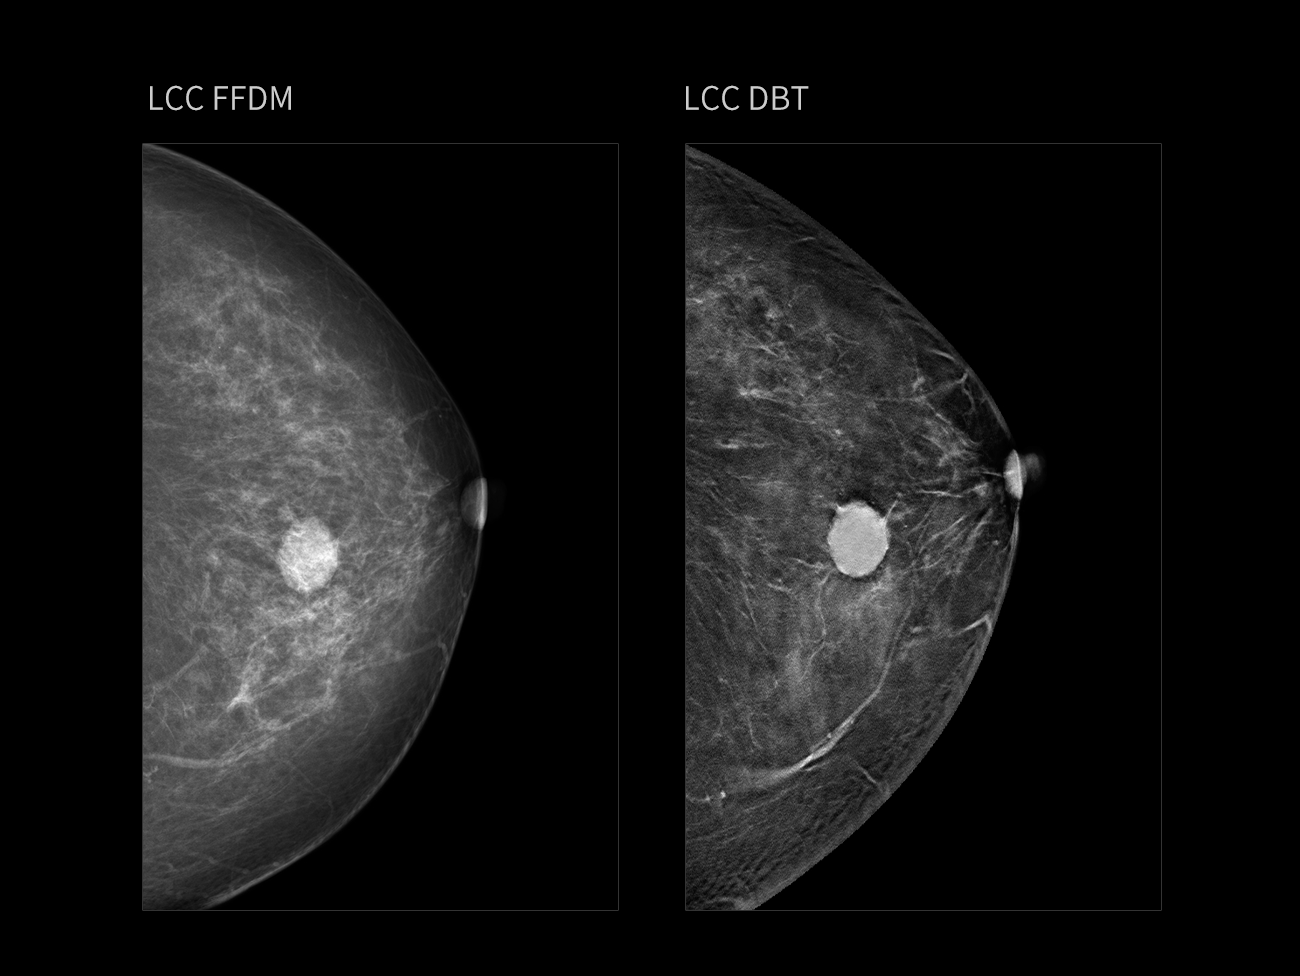

Masă

Sân fibroglandular dens, cu o grosime de 61 mm.

FFDM evidențiază clar o masă palpabilă densă, neregulată, în zona mijlocie a sânului stâng postero-inferior, cu margini neclare și lobuli vizibili. DBT arată mai clar hiperplazia glandulară, cu multiple noduli mici și câteva calcificări punctiforme.